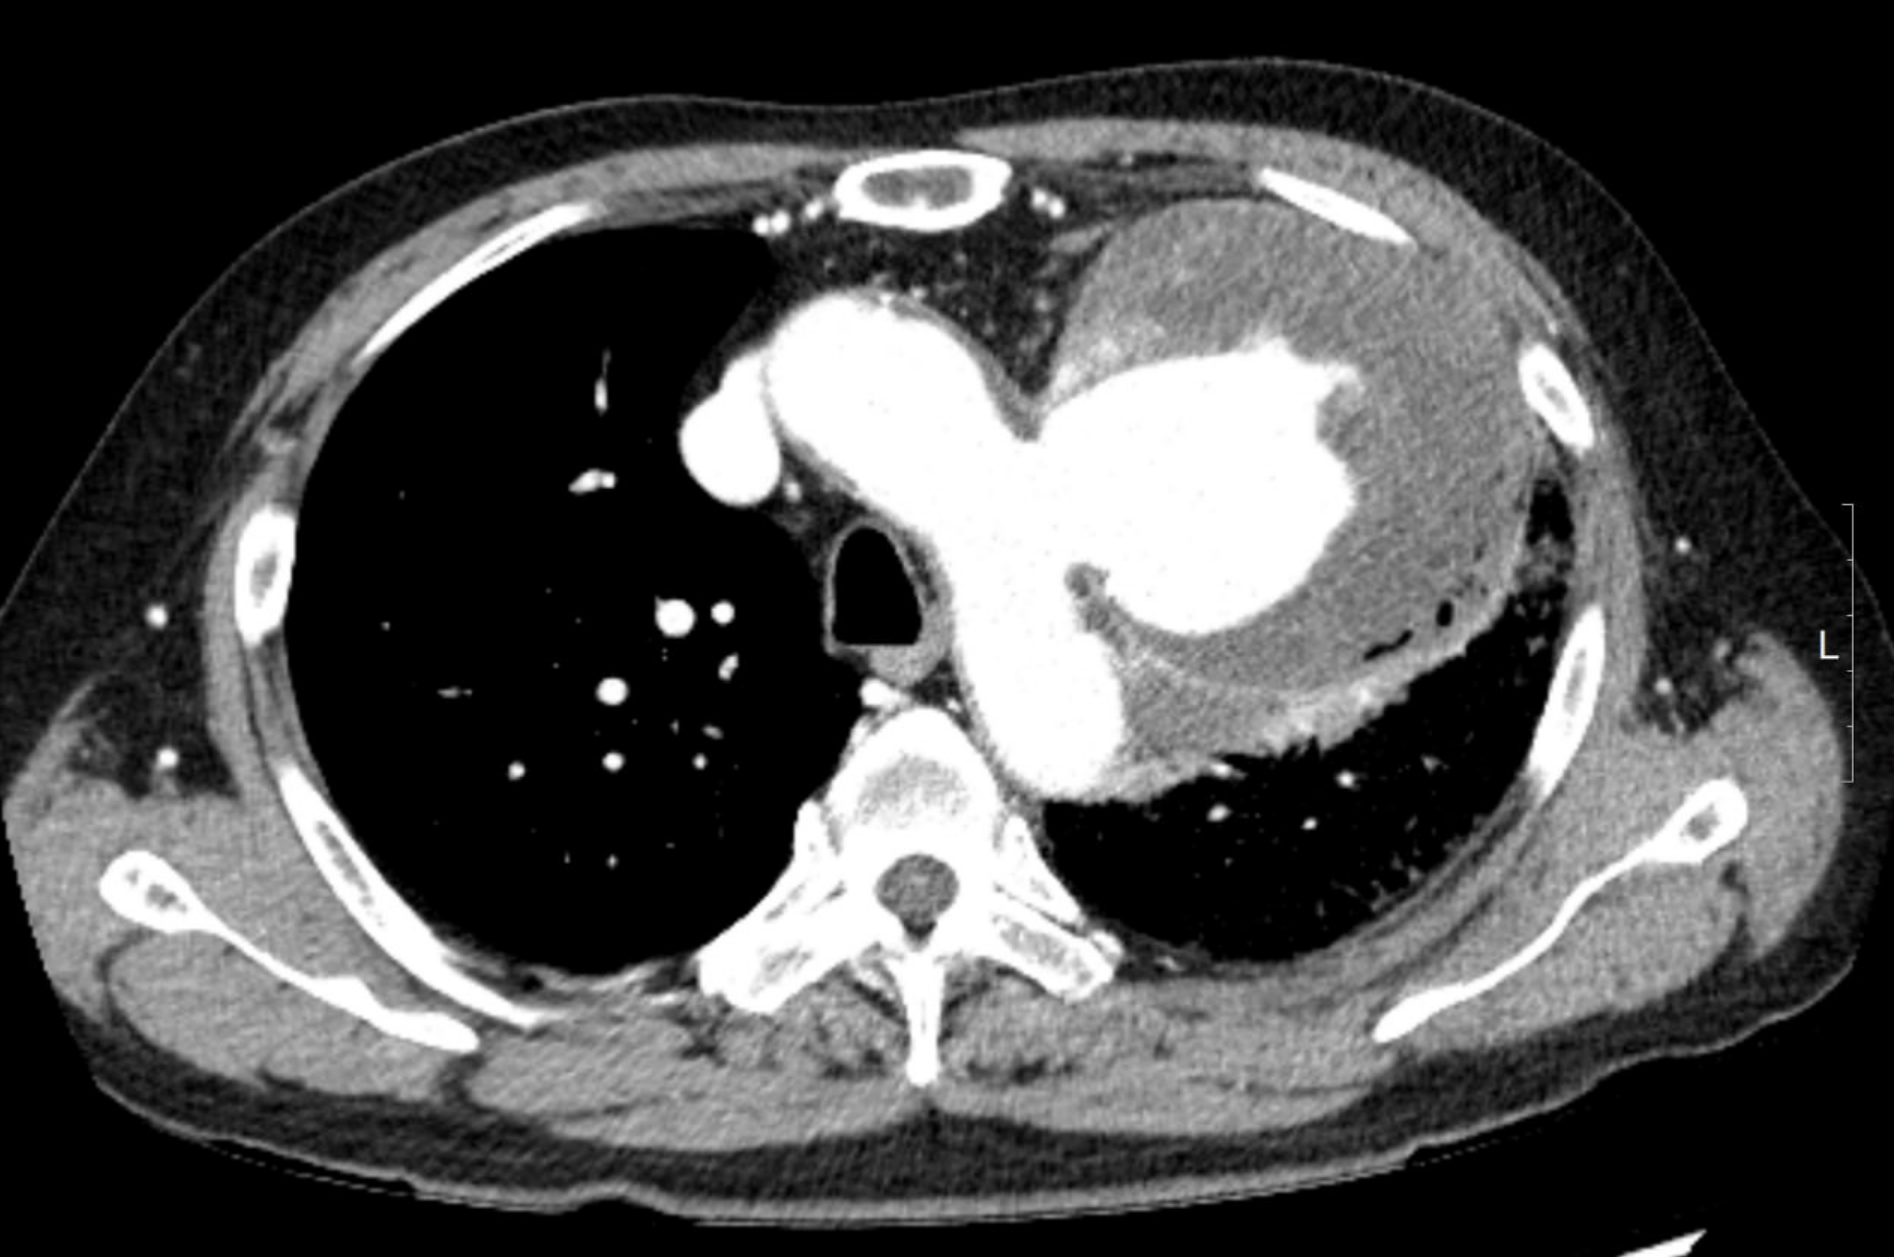

hematemsis(119) -> hemoptysis 로 판명 (L tube clear)

Result)

Expire